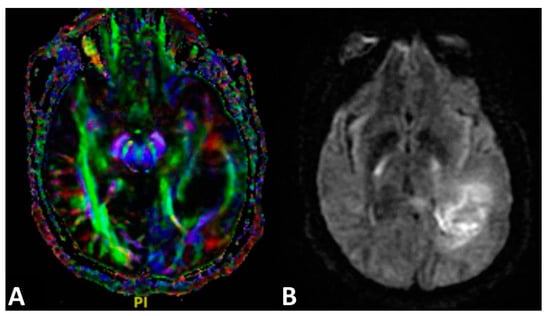

4.3. Diffusion Tensor Imaging

- Cha, S. Neuroimaging in Neuro-Oncology. Neurotherapeutics 2009, 6, 465–477. [Google Scholar] [CrossRef]